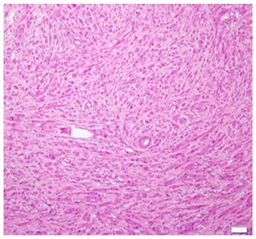

An excision biopsy specimen from a mass at elbow of 26 years old female patient was received for histopathological examination. The clinical impression was of ‘benign soft tissue tumor’. The specimen was received in 10% formalin in one container. On gross examination, it was a 1.5 x 1 x 0.5 cm well-circumscribed, grey-tan mass, without skin component. The cut surface was solid homogenous and no necrotic or hemorrhagic areas were found on it. The microscopic examination revealed a circumscribed encapsulated lesion composed of round to polygonal to spindle shaped cells with eosinophilic granular cytoplasm and centrally placed small nuclei (Figure 1 & Figure 2). Cells were arranged in intersecting bundles and mixed with fibrous connective tissue (Figure 3). The Intralesional peripheral nerve bundles surrounded by the lesional cells were seen (Figure 4). No significant mitoses or cells with cross striation, significant inflammatory infiltrate or necrosis were seen. IHC showed positive results for S100 (Figure 5) and neuron-specific Enolase (NSE) (Figure 6). Smooth muscle actin (SMA) (Figure 7) and Myogenin were negative. CEA was focally positive. Periodic acid-schiff (PAS) stain showed PAS positive intracytoplasmic granules (Figure 8). The lesion was completely excised with <1mm safety margin. Focal entrapment of the adjacent fatty tissue was observed. Based on the above mentioned findings, diagnosis of granular cell tumor (GCT) was made.

Figure 3 Cells were arranged in intersecting bundles and mixed with fibrous connective tissue.